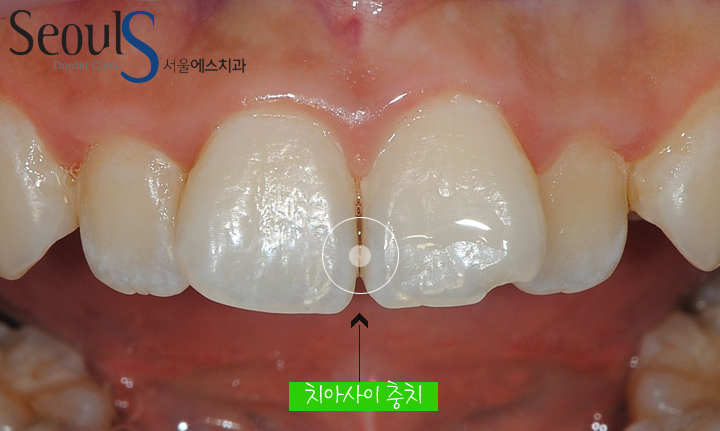

치아 앞면입니다

원으로 표시한 부분에 충치가 진행되고 있습니다

앞니는 치아 사이에 음식물이 꼈을때 진행되는 경우가 많습니다

치아 사이에 진행되는 충치는 치아 속으로 진행되기 때문에 발견하기 쉽지 않은데요